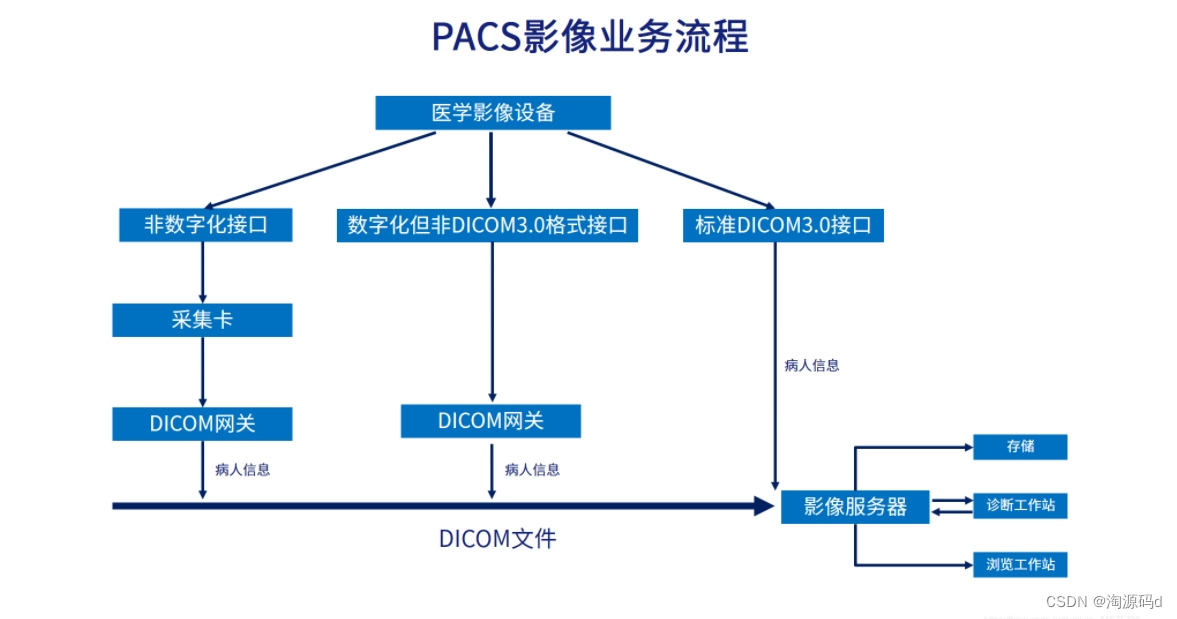

PACS系统以实现医学影像数字化存储、诊断为核心任务,从医学影像设备(如CT、CR、DR、MR、DSA、RF等)获取影像,集中存储、综合管理医学影像及病人相关信息,建立数字化工作流程。

·开放式体系结构,完全符合DICOM3.0标准,提供HL7标准接口,可实现与提供相应标准接口的HIS系统以及其他医学信息系统间的数据通信。

数字采集

支持DICOM3.0标准的数据收发及自动转发

支持非DICOM3.0标准的数据接收